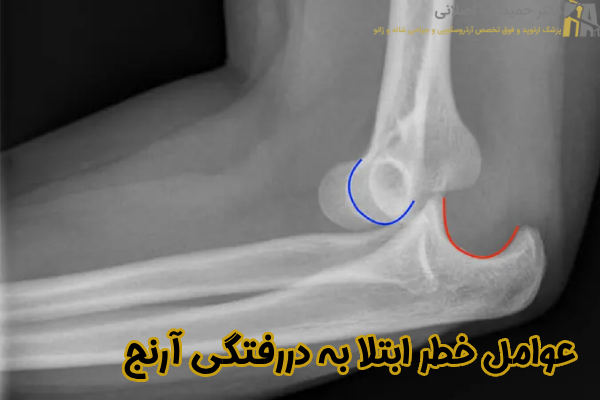

عوامل خطر ابتلا به دررفتگی مفصل آرنج دست

در ادامه به مهمترین عوامل خطر در رفتگی آرنج اشاره می نماییم:

- افزایش سن: افراد مسن تر به ویژه بالای 65 سال، به دلیل ضعف عضلات و افزایش احتمال زمین خوردن بیشتر در معرض این آسیب دیدگی قرار دارند.

- فعالیت های ورزشی شدید: ورزش هایی که فشار زیادی به آرنج وارد می کنند مانند بیس بال، ژیمناستیک یا وزنه برداری، ریسک دررفتگی را افزایش می دهند.

- سن پایین و رشد فعال: در کودکان و نوجوانان، به دلیل رشد سریع و مفاصل انعطاف پذیرتر احتمال دررفتگی در اثر ضربه یا کشش ناگهانی بیشتر می شود.

- شرکت در فعالیت های ورزشی: افرادی که در ورزش هایی مانند فوتبال، راگبی یا کشتی شرکت می کنند نیز به دلیل تماس های فیزیکی مکرر بیشتر در معرض این آسیب دیدگی قرار دارند.

- انعطاف پذیری بیش از حد مفصل: افرادی که به صورت مادرزادی رباط های شل دارند مانند مبتلایان به سندرم Ehlers-Danlos، احتمال بیشتری برای دررفتگی مفاصل دارند.